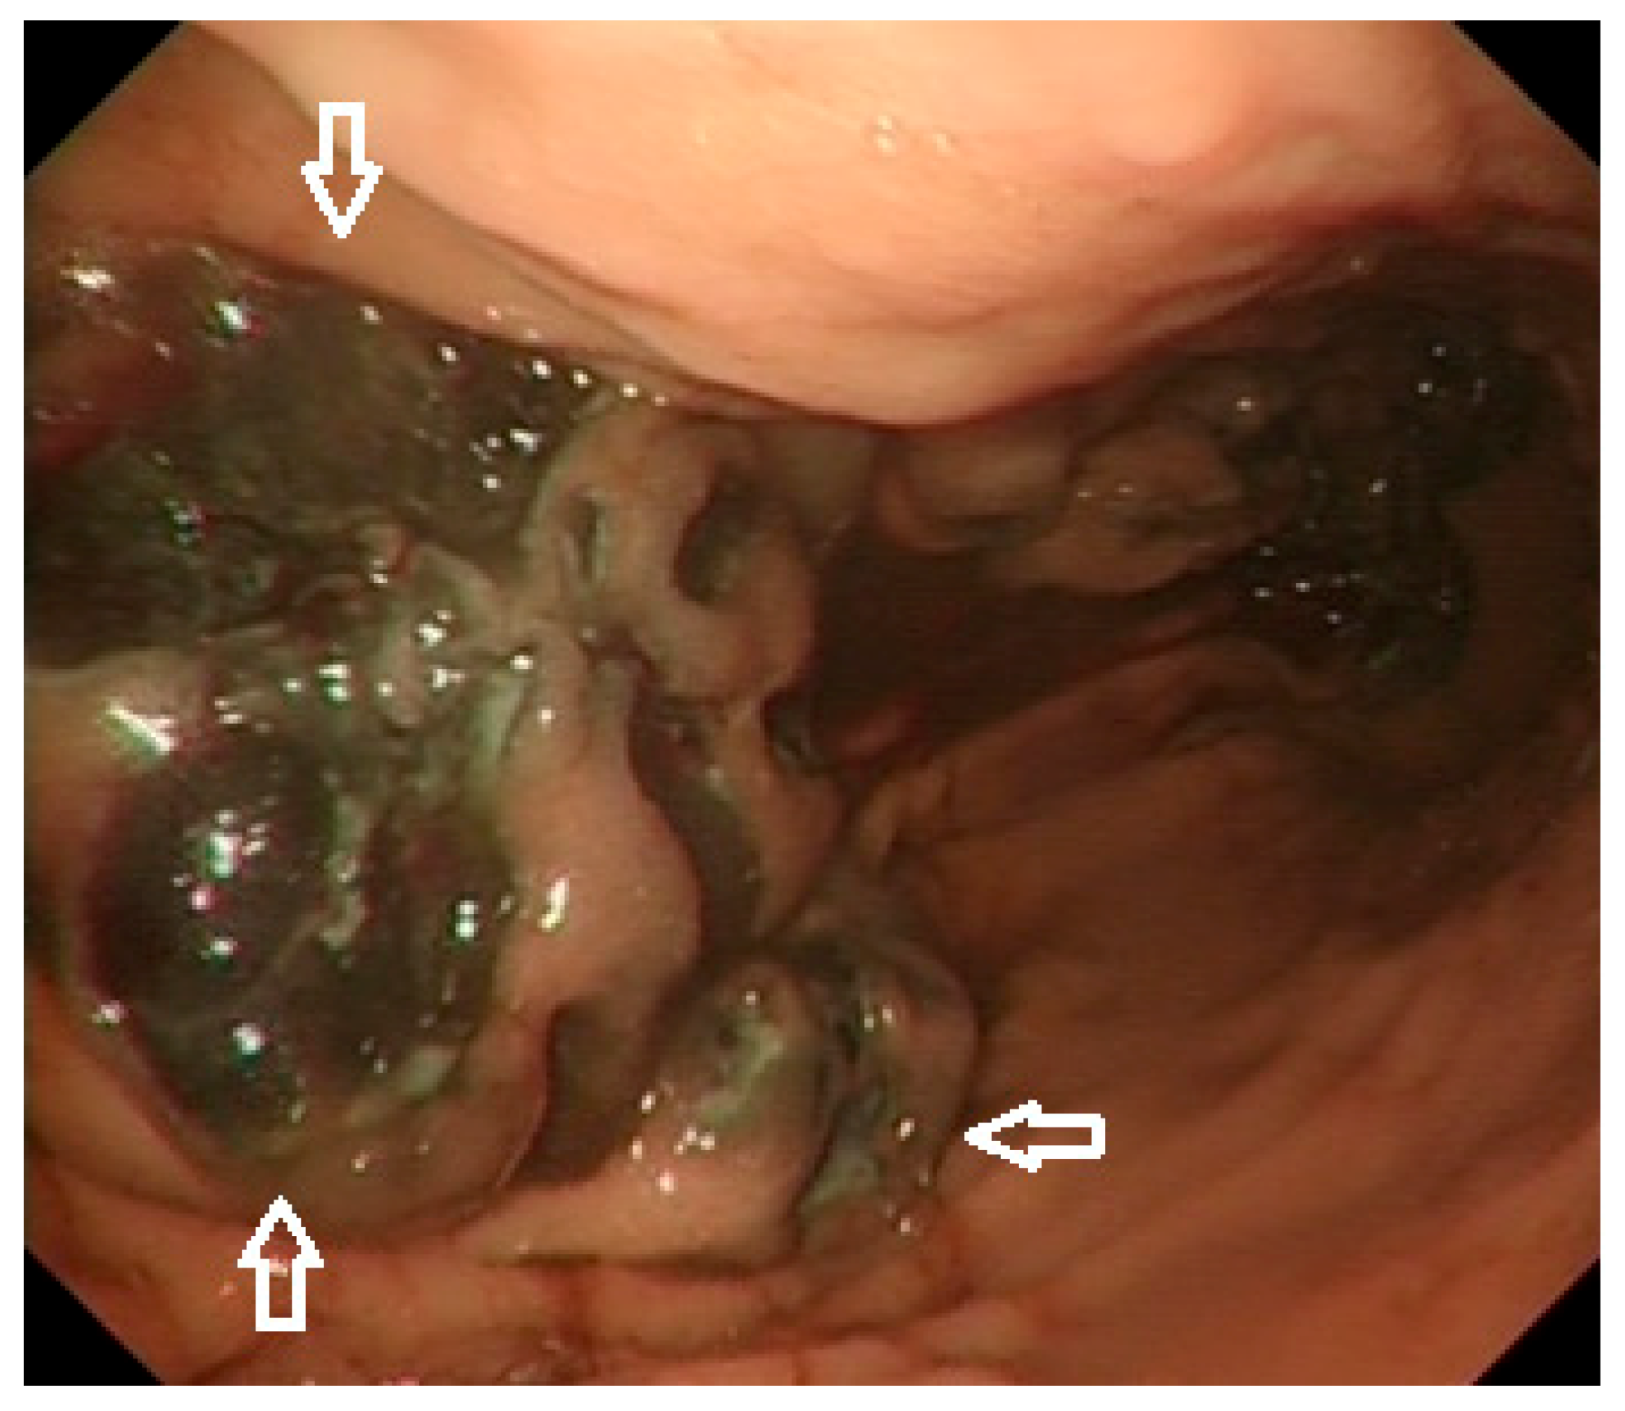

1.4. Diagnosis

1.6.1. Endoscopy